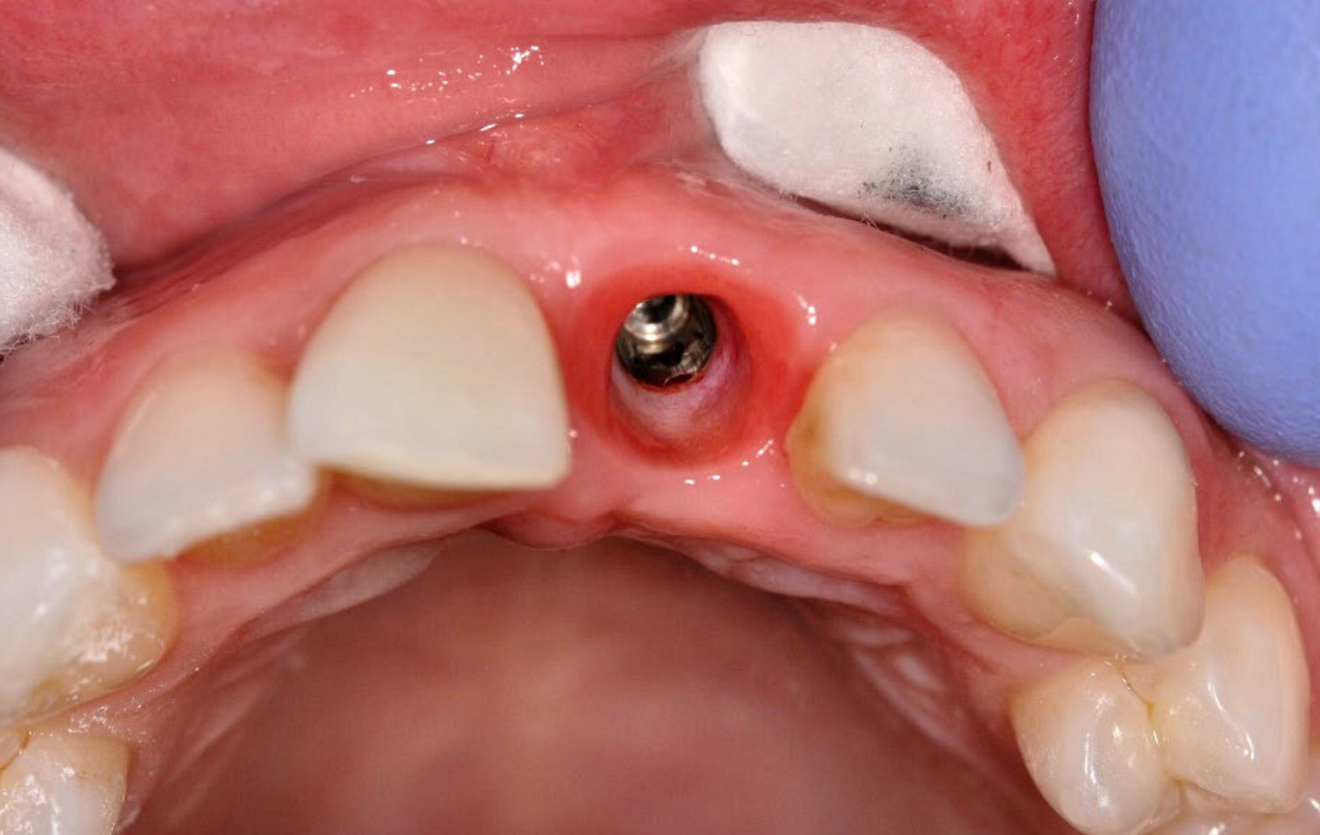

Healing abutment (e) ...

... and the resulting contoured tissue at 12 weeks post-op (f).